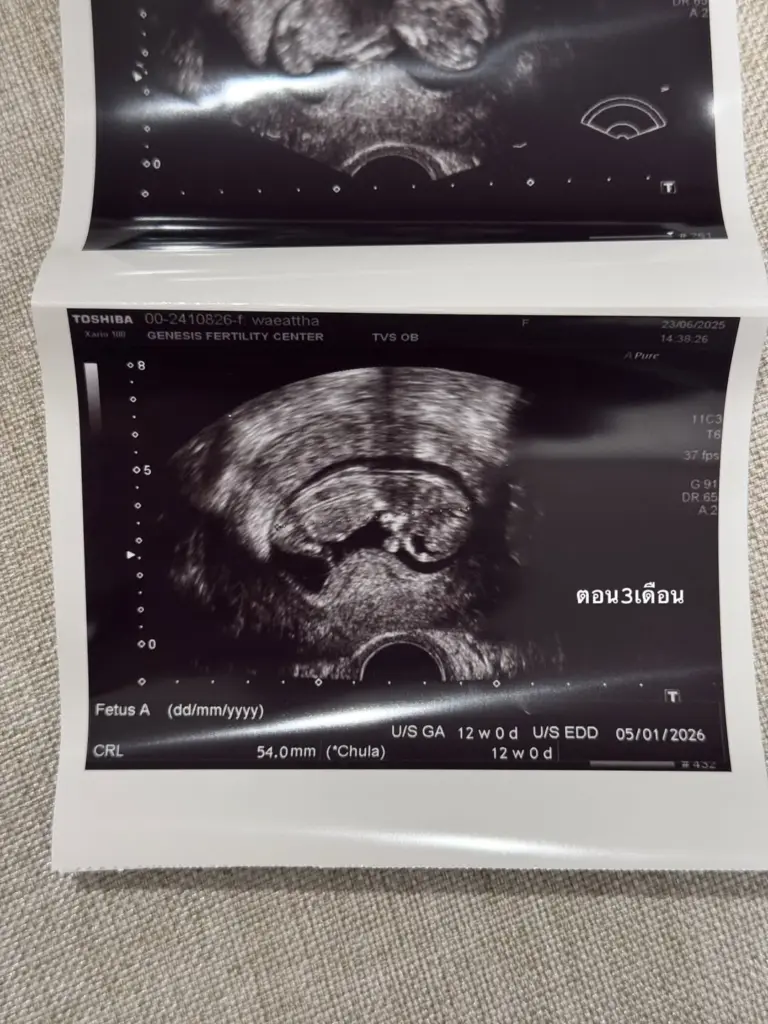

และความพยายามก็ไม่สูญเปล่า เพราะตอนนี้เจ้าตัวน้อยในท้องแข็งแรงมาก ถึงขั้นดิ้นเก่งตั้งแต่ 3 เดือนแรก งานนี้คุณแม่คนสวยก็ยิ้มได้อย่างเต็มที่ พร้อมส่งต่อพลังบวกให้กับว่าที่คุณแม่คนอื่นๆ ด้วยความหวังและกำลังใจ

ภาพจาก : warutthaim